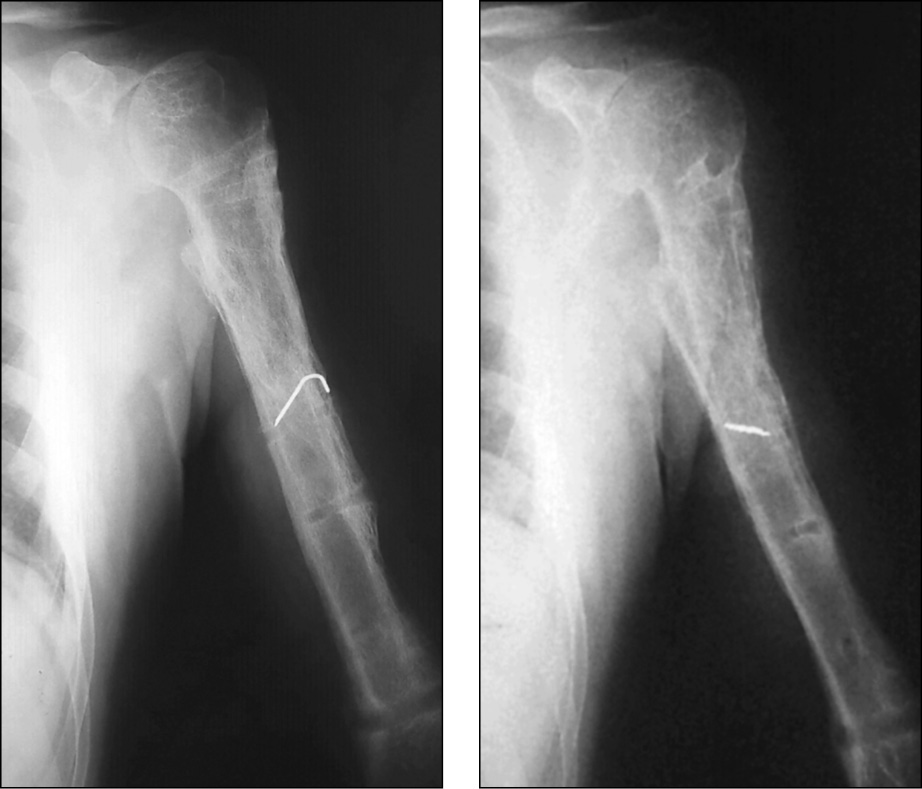

Пациент, 49 лет, получил производственную травму в результате падения с высоты около 2 м. Диагноз: «Закрытый перелом на границе верхней и средней трети левой плечевой кости». Через 5 дней после травмы выполнен остеосинтез пластиной и винтами. Спустя месяц открылся свищ, в связи с чем произведено удаление металлоконструкции, секвестрнекрэктомия и реостеосинтез левой плечевой кости аппаратом внешней фиксации. Аппарат демонтирован через 6 мес. В последующем выполнялись неоднократные санационные операции левой плечевой кости по поводу рецидива в разных лечебных учреждениях (рис. 5).

Рис. 5. Послеоперационные рентгенограммы левой плечевой кости после секвестрнекрэктомии